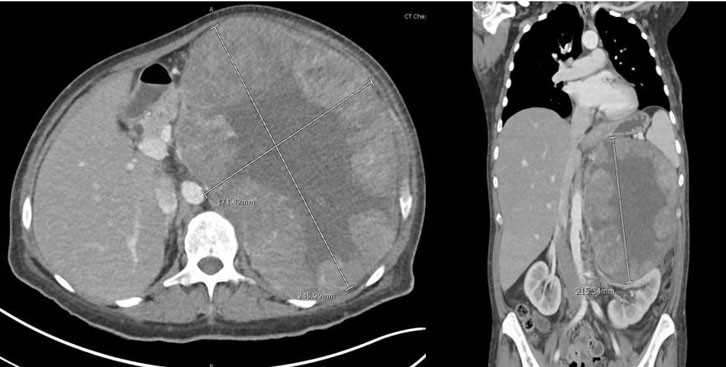

A previously healthy 45-year-old woman was admitted to the hospital for left-sided abdominal pain, significant weight loss of about eighty pounds over seven-month period, along with mild endocrine abnormalities. Pertinent physical exam findings included a large protuberant abdomen with palpable mass occupying the entire left upper quadrant; however, she did not have hirsutism, signs of virilization, or cushingoid features. Initial imaging revealed that she had a large left adrenal mass measuring 24.6 × 21.5 × 17.1 cm, with central necrosis and heterogeneous enhancement (Figure 1 and Figure 2). A 24-hour urinary free cortisol level was 74 μg/24 h, which indicated mild hypercortisolism. DHEAS was elevated at 325 μg/dL, suggestive of androgen overproduction without clinical signs of virilization. The urinary metanephrines were normal and normetanephrines were slightly elevated and measured at 1.5 nmol/L, indicating no evidence of pheochromocytoma. Additionally, the patient exhibited non-PTH-mediated hypercalcemia (total serum corrected calcium 11.4 mg/dL). Skeletal metastasis was ruled out with nuclear medicine bone scan. A multidisciplinary tumor board recommended an en-bloc surgical resection accounting for the size of the mass and radiographic features that were indicative of malignancy. The patient underwent a left adrenalectomy combined with a left nephrectomy, distal pancreatectomy, splenectomy, and extended lymphadenectomy via a chevron incision. The patient’s multiorgan resection successfully cleared the lesion, yielding negative margins and removing 54 lymph nodes, all pathologically negative. This underscores that even with large adrenal masses, nodal spread may be absent if the tumor’s proliferative index is relatively low. Early vascular control near the renal hilum was established to minimize hemorrhagic risk. The surgery was complicated by an estimated blood loss of 2.5 L, requiring intraoperative transfusions. Postoperatively, the patient received stress-dose hydrocortisone to mitigate the risk of adrenal insufficiency. After discharge, the patient was started on external beam radiation therapy for five weeks and identified for long-term surveillance. The patient did not receive adjuvant therapy with mitotane. Subsequent imaging completed three months after completion of radiation therapy revealed no evidence of tumor recurrence. Corrected serum calcium at the same time was 10.0 mg/dL. The patient is currently being closely followed up in the endocrinology clinic for steroid taper.

Figure 1: Radiographic imaging at presentation.